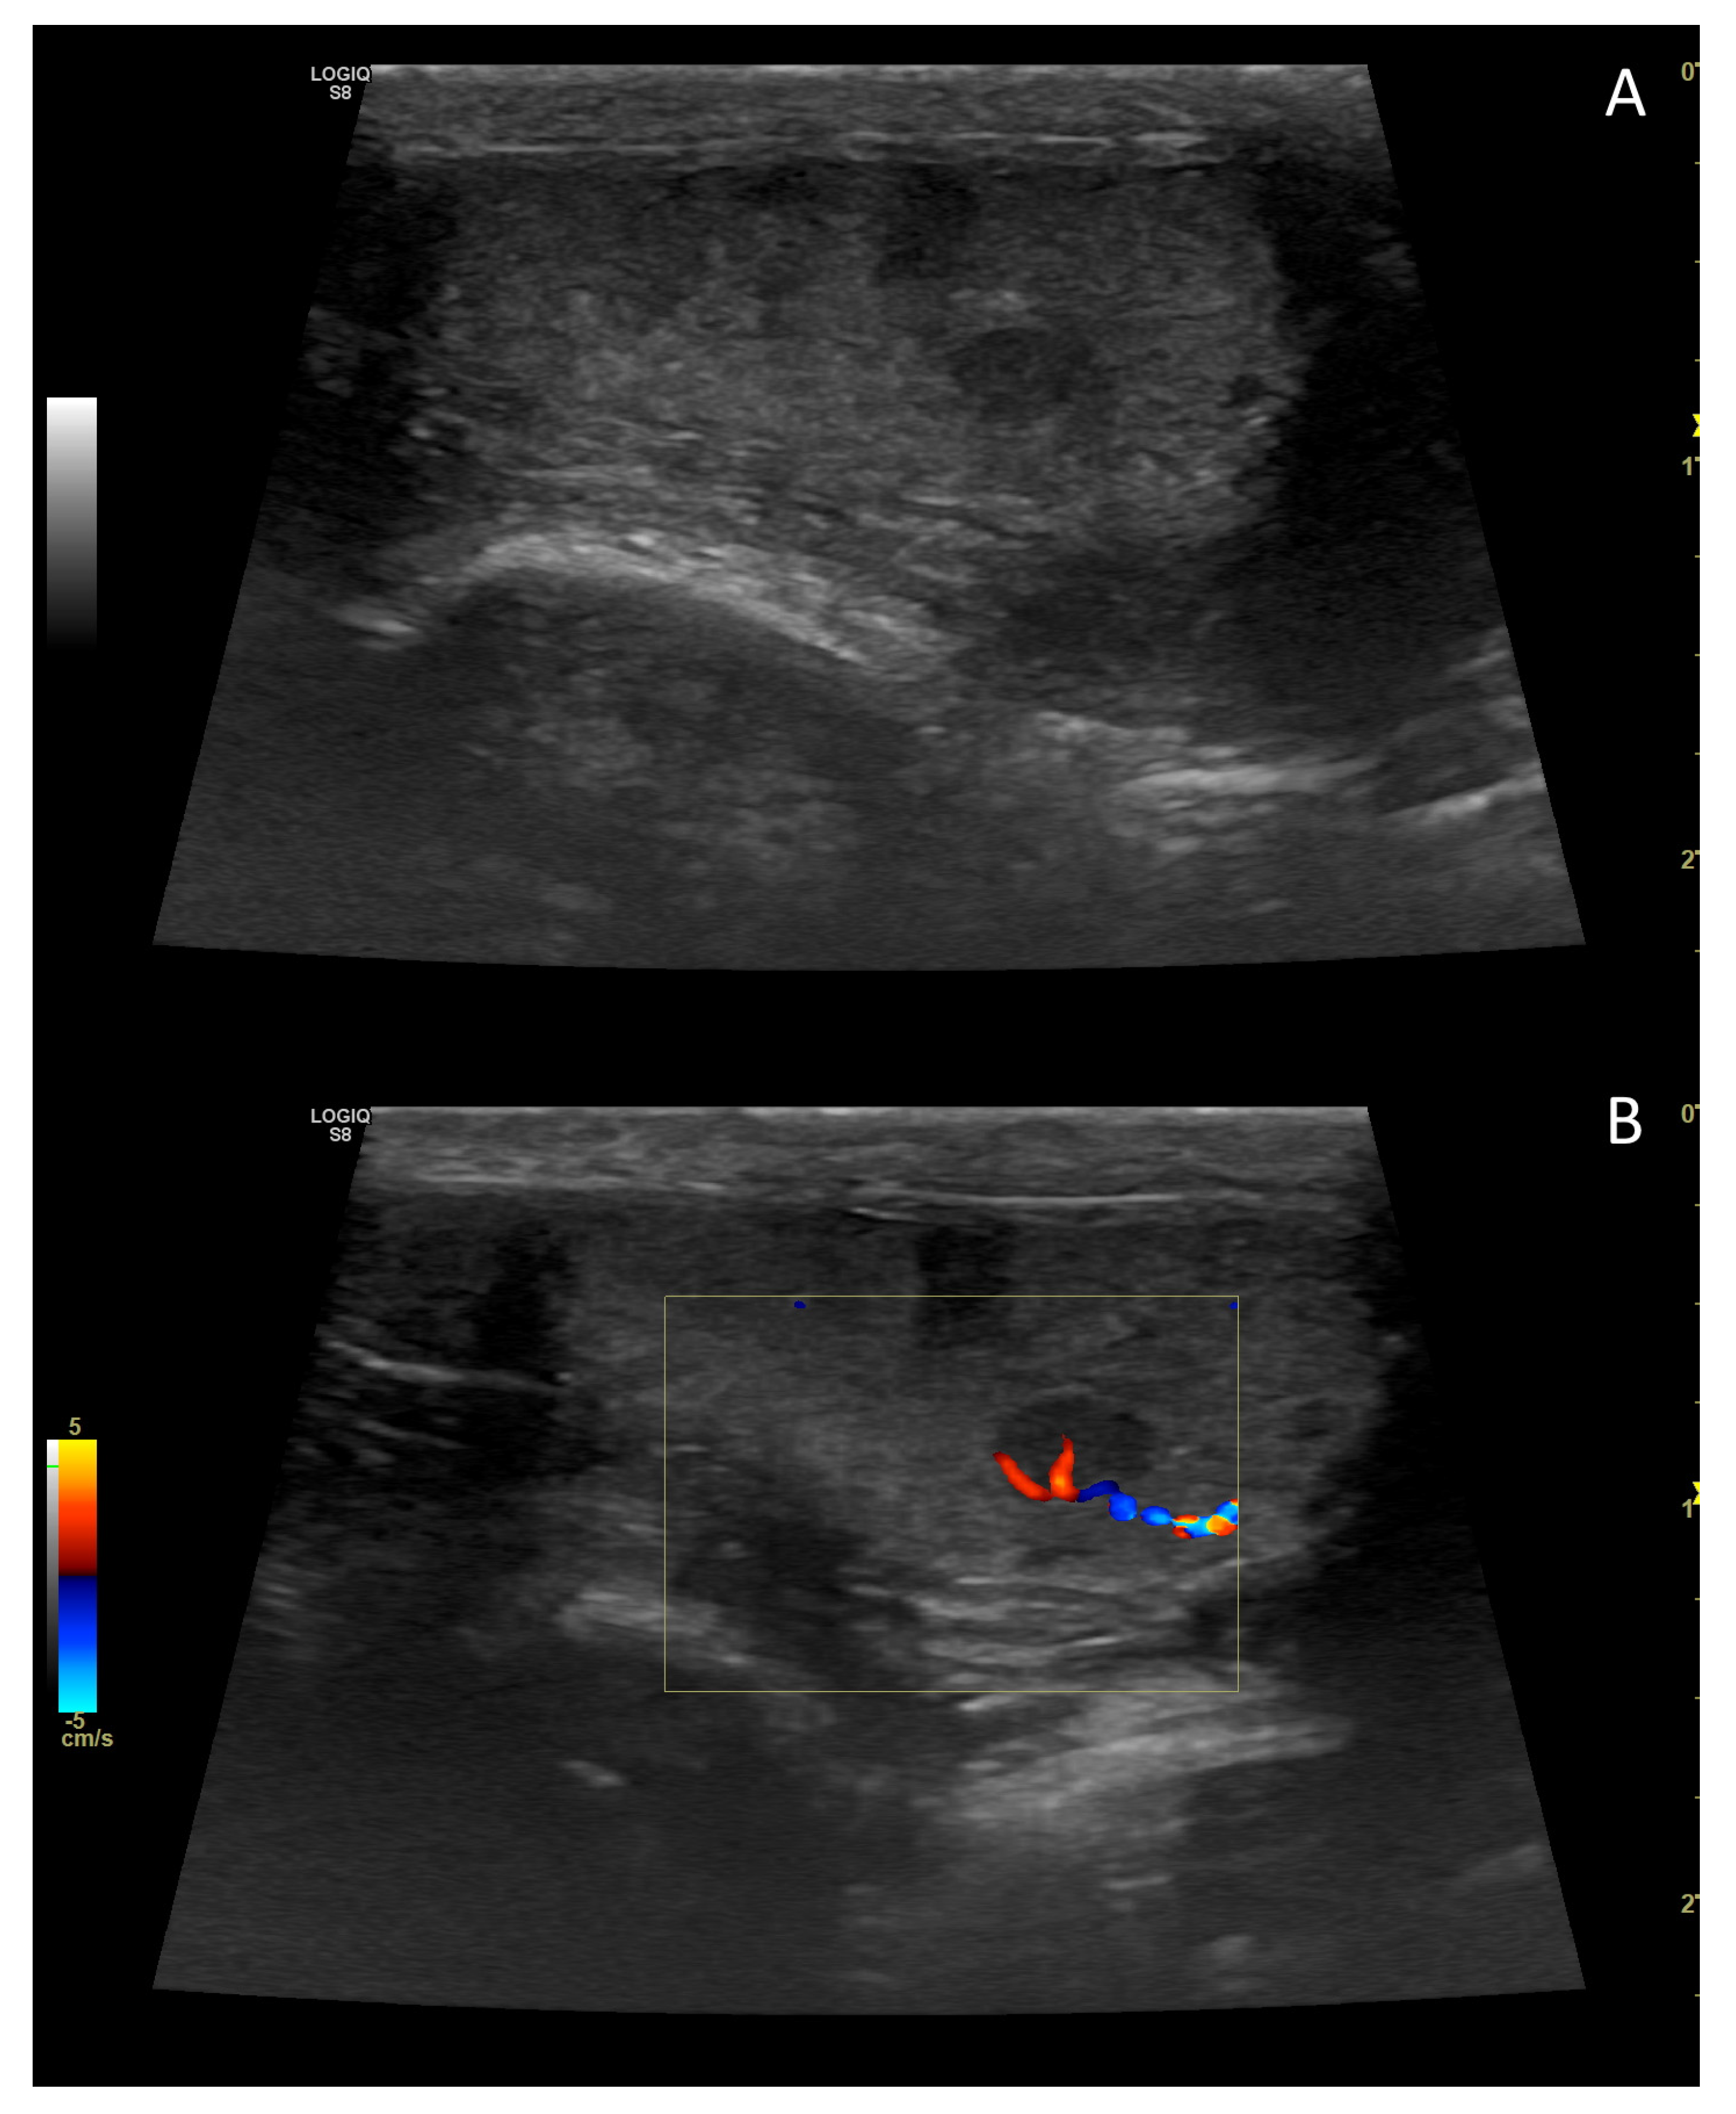

4. Colour Doppler and Power Doppler

4.2. Normal Findings

4.4. Abnormal Findings